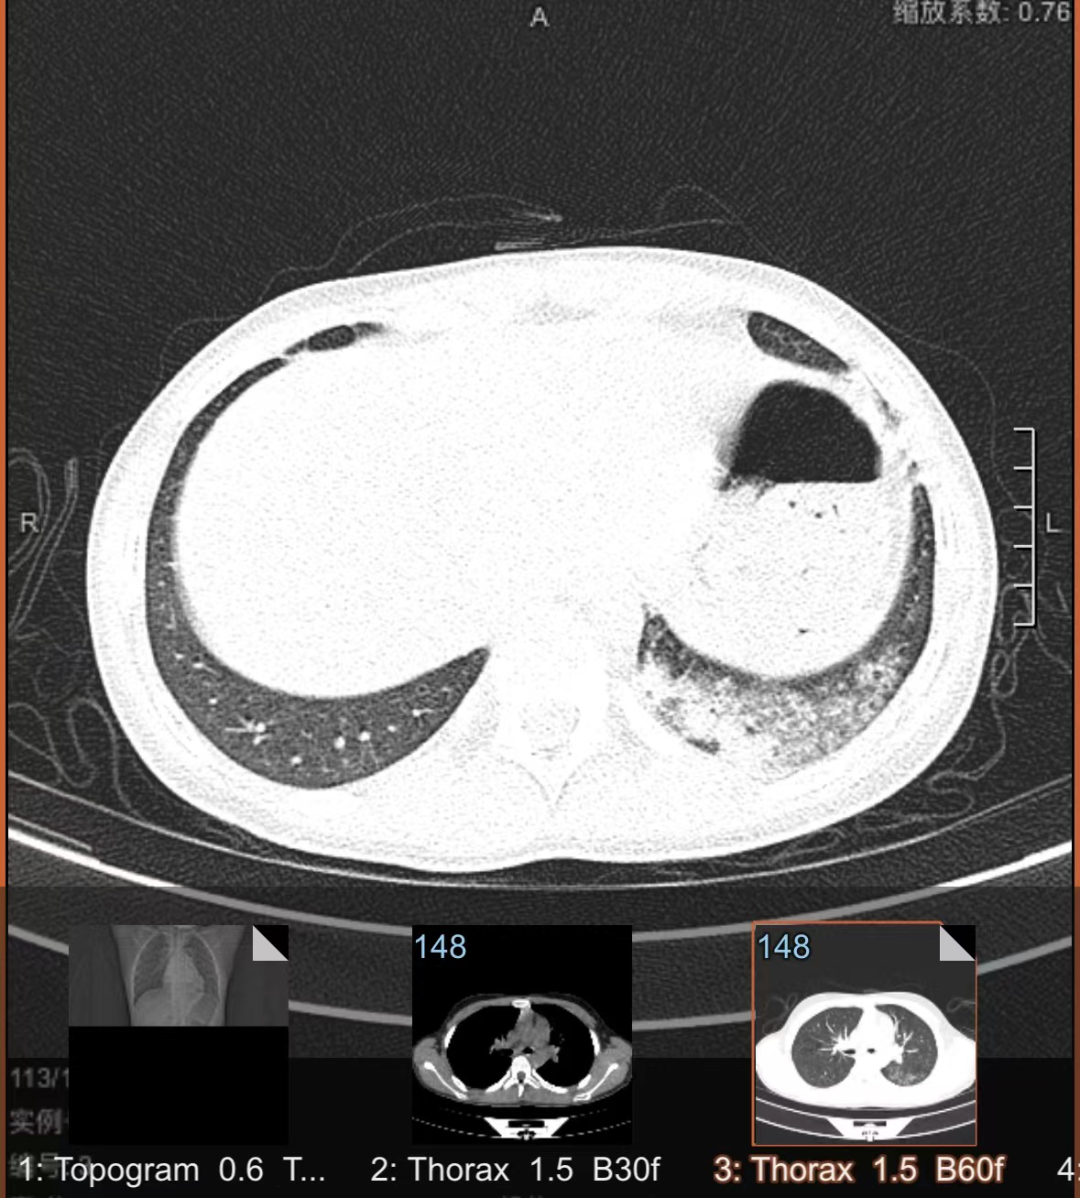

一拍片发现肺部出现了炎症

还融合成了片状

支原体呼吸道感染临床表现呈多样性,可从无无症状到鼻咽炎、鼻窦炎、中耳炎、扁桃体炎、气管支气管炎和肺炎等,肺炎支原体肺炎的主要临床表现是发热、咳嗽、肺部体征与临床症状及影像所见不一致。

除呼吸系统外,支原体肺炎可伴发多系统、多器官损害。皮肤损害可表现为斑丘疹、结节性红斑等,胃肠道系统多以呕吐、腹泻及肝功损害为主,血液系统多以溶血性贫血多发,中枢神经系统损害可见多发性神经根炎、脑膜脑炎及小脑损伤等。

只有少部分感染者会发展为肺炎。肺炎支原体肺炎(MPP)以发热、咳嗽为主要临床表现,可伴有头痛、流涕、咽痛、耳痛等。发热以中高热为主,持续高热者预示病情重。咳嗽较为剧烈,可类似百日咳样咳嗽,婴幼儿以喘息为主要表现多见。肺部早期体征可不明显,随着病情进展可出现呼吸音降低和干、湿性啰音。